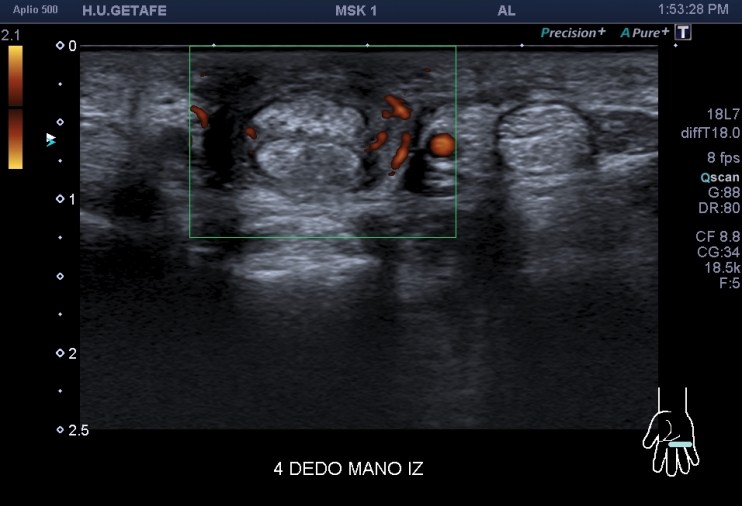

La imagen 4 y 5 reflejan la neovascularización asociada a algunos procesos como este. Igualmente preciosa.

Estas imágenes hablan por si mismas, el atrapamiento lo puedes ver en este Vídeo en el Canal de Instagram del Blog. Vas a entender perfectamente el sentido del Post y lo bonito que fue para mi poder hacer este caso que te quiero mostrar esta noche.